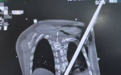

随后,全身CT扫描如同绘制一份精准的“体内战场地图”,清晰显示:钢筋险之又险地穿过腹膜后间隙,击穿了胸腰段的脊柱椎管,导致患者当时双下肢已无法活动,最终穿入胸腔。更危险的是,它的路径紧贴肾脏、大血管,每一次心跳都可能让钢筋的锋刃与血管摩擦,引发灾难性大出血。